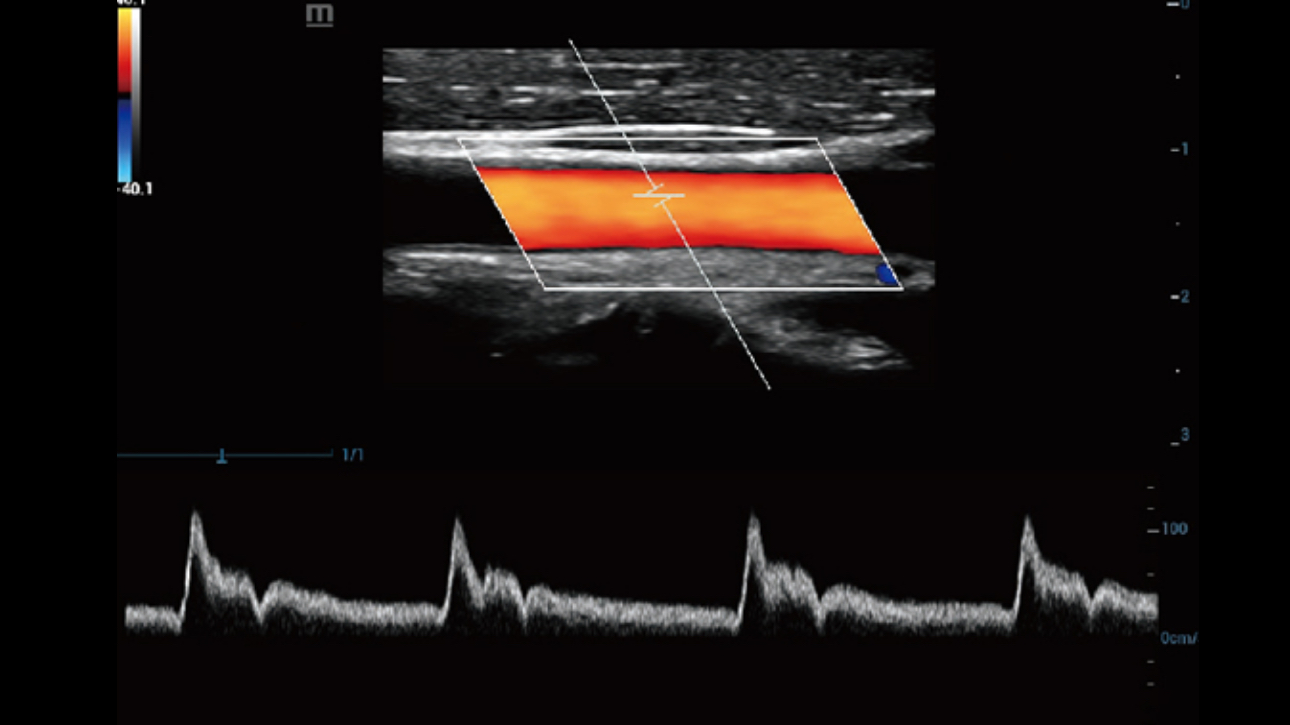

By transmitting and receiving a relatively smaller number of large zones, Advanced Acoustic Acquisition extracts more information from each acquisition, 10 times faster than a conventional line-by-line beamforming method.